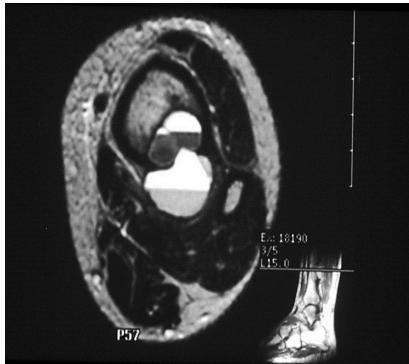

Aneurysmal Bone Cyst

site: Distal tibial

size: Involving most of distal part

matrix: Cortical expansion, radiolucent matrix, well defined, narrow zone of transition

soft tissue involvement: no peristeal reaction